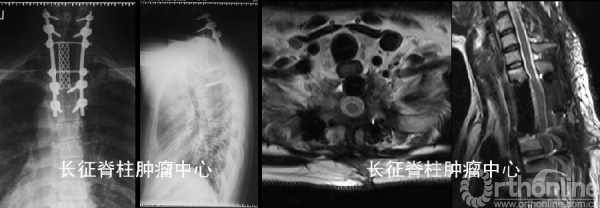

(1)导航辅助下后路胸1-3肿瘤En bloc切除重建内固定术

(2)术后处理:常规伤口换药引流、预防感染、支持治疗。病理报告:骨巨细胞瘤复发(初次手术病理不准确,可能与样本量小有关)。床上肢体功能锻炼,术后3周在支具保护下逐渐下地行走。

✦术后随访:

术后胸背疼痛症状缓解。行双磷酸盐治疗,术后1年随访未见肿瘤复发,内固定在位良好。